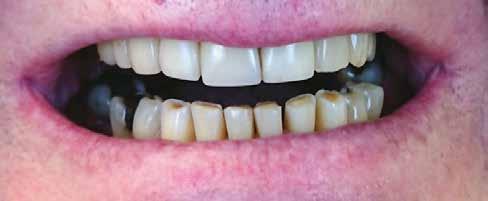

A cikkben egy fiatal nő kezelésének interdiszciplináris megközelítését foglaltuk össze, aki fogászati állapota miatt hoszszú ideje szenvedett fizikálisan és pszichésen is (1. ábra)

Amikor a 25 éves Andrea először konzultált a rendelővel, már több éve küszködött súlyos panaszokkal. Állapota két különböző betegségnek köszönhető, melyek egyrészt önmagukban, másrészt egymással kölcsönhatásban is súlyos következményekkel jártak. A fiatal nő veleszületett genetikai elváltozásban szenved, melynek tünete többek között a gyenge zománcfejlődés. Továbbá a beteget fibromyalgiával is diagnosztizálták, mely krónikus fájdalom rendellenesség, ami komoly tünetegyüttessel járó pszichés szorongás. A betegség egyik következménye az volt, hogy a páciens az elmúlt években átlagosan napi három-négyszer hányt. Az ebből fakadó savas erózió a már amúgy is veszélyben lévő fogazatot tovább roncsolta (2. ábra)

A páciens elviselhetetlen fájdalmakról számolt be, beleértve a többszörös szájüregi fertőzéseket is. Az elmúlt években az előírt számos antibiotikumos kezelés egyre gyengébb hatásfokkal működött. A fertőzések következtében több fogát is extrahálni kellett. A fogászati állapotával együtt az étkezés minősége is romlott. A súlyos esztétikai korlátok is terhet jelentettek. A psziché és az önbizalom komoly károkat szenvedett. Fogorvosnál tett korábbi látogatásai kellemetlen élményt jelentettek. Emiatt kezdetben vonakodott beleegyezni a komplex terápiába. Empatikus, érzékeny beszélgetések folyamán körvonalazódott számára a kezelés fontossága.